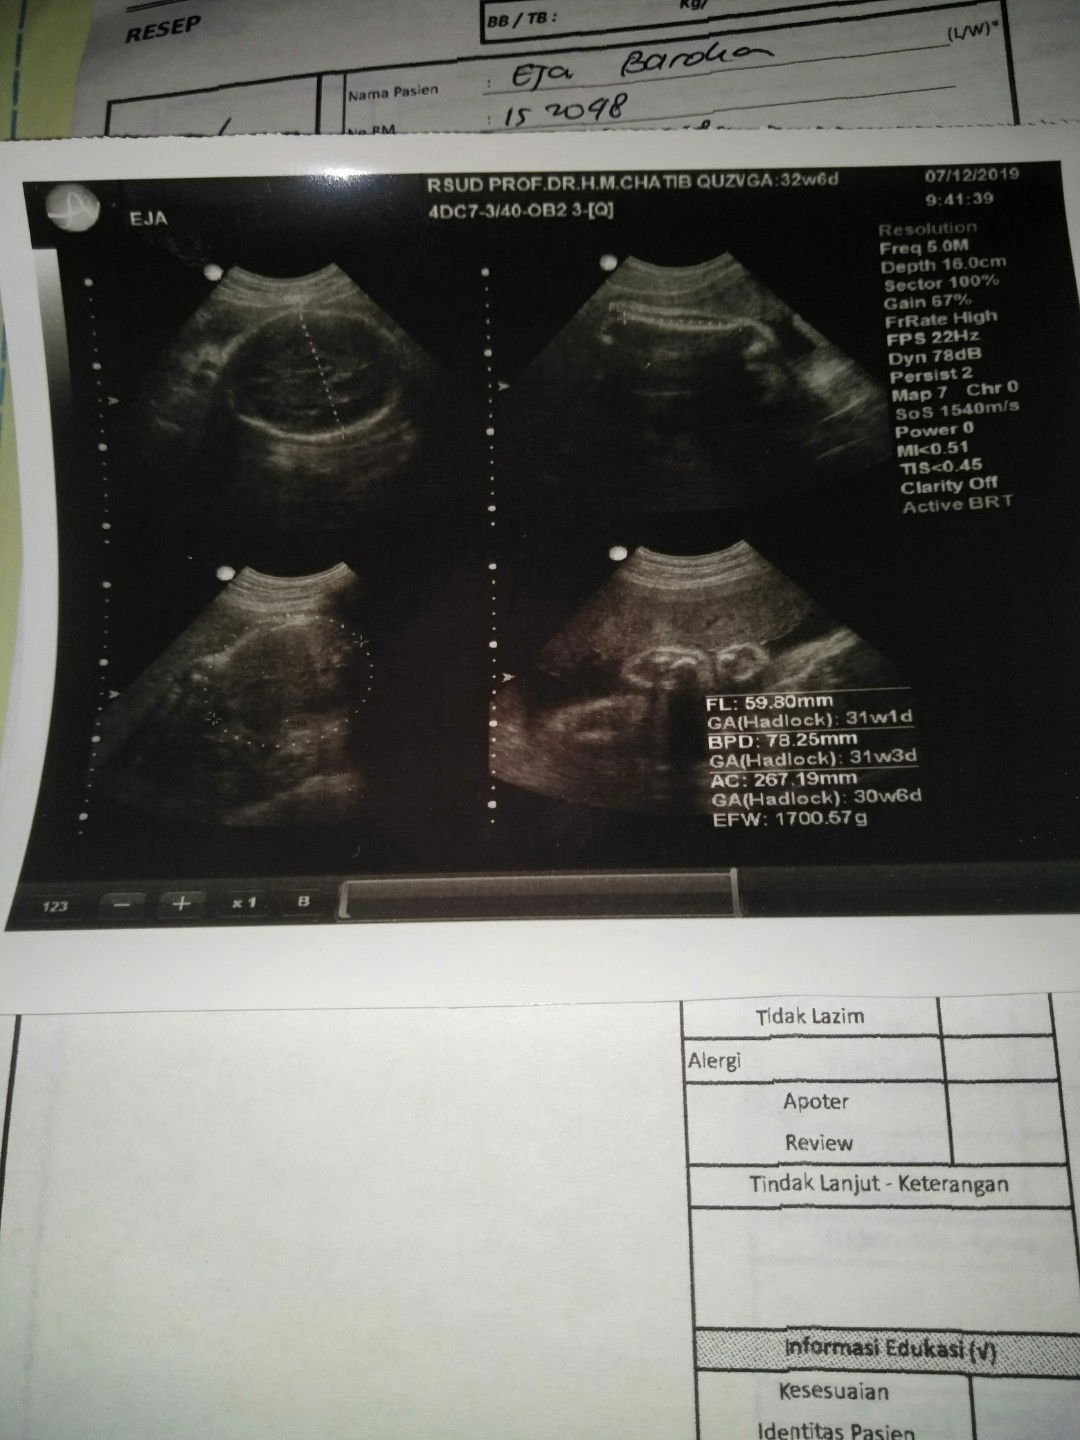

Assalamualaikum selamat siang bund Kita sharing yuk yg Hpl nya samaan sama saya januari 2020 nanti ? Kalo saya hpl 26 januari 2020 ,bbj nya udah 1700g trus insyaallah baby girl bund Kalo bunda2 gimana? Smoga kita di mudahkan dan dilancarkan saat persalinan nanti y bund ? amiinn